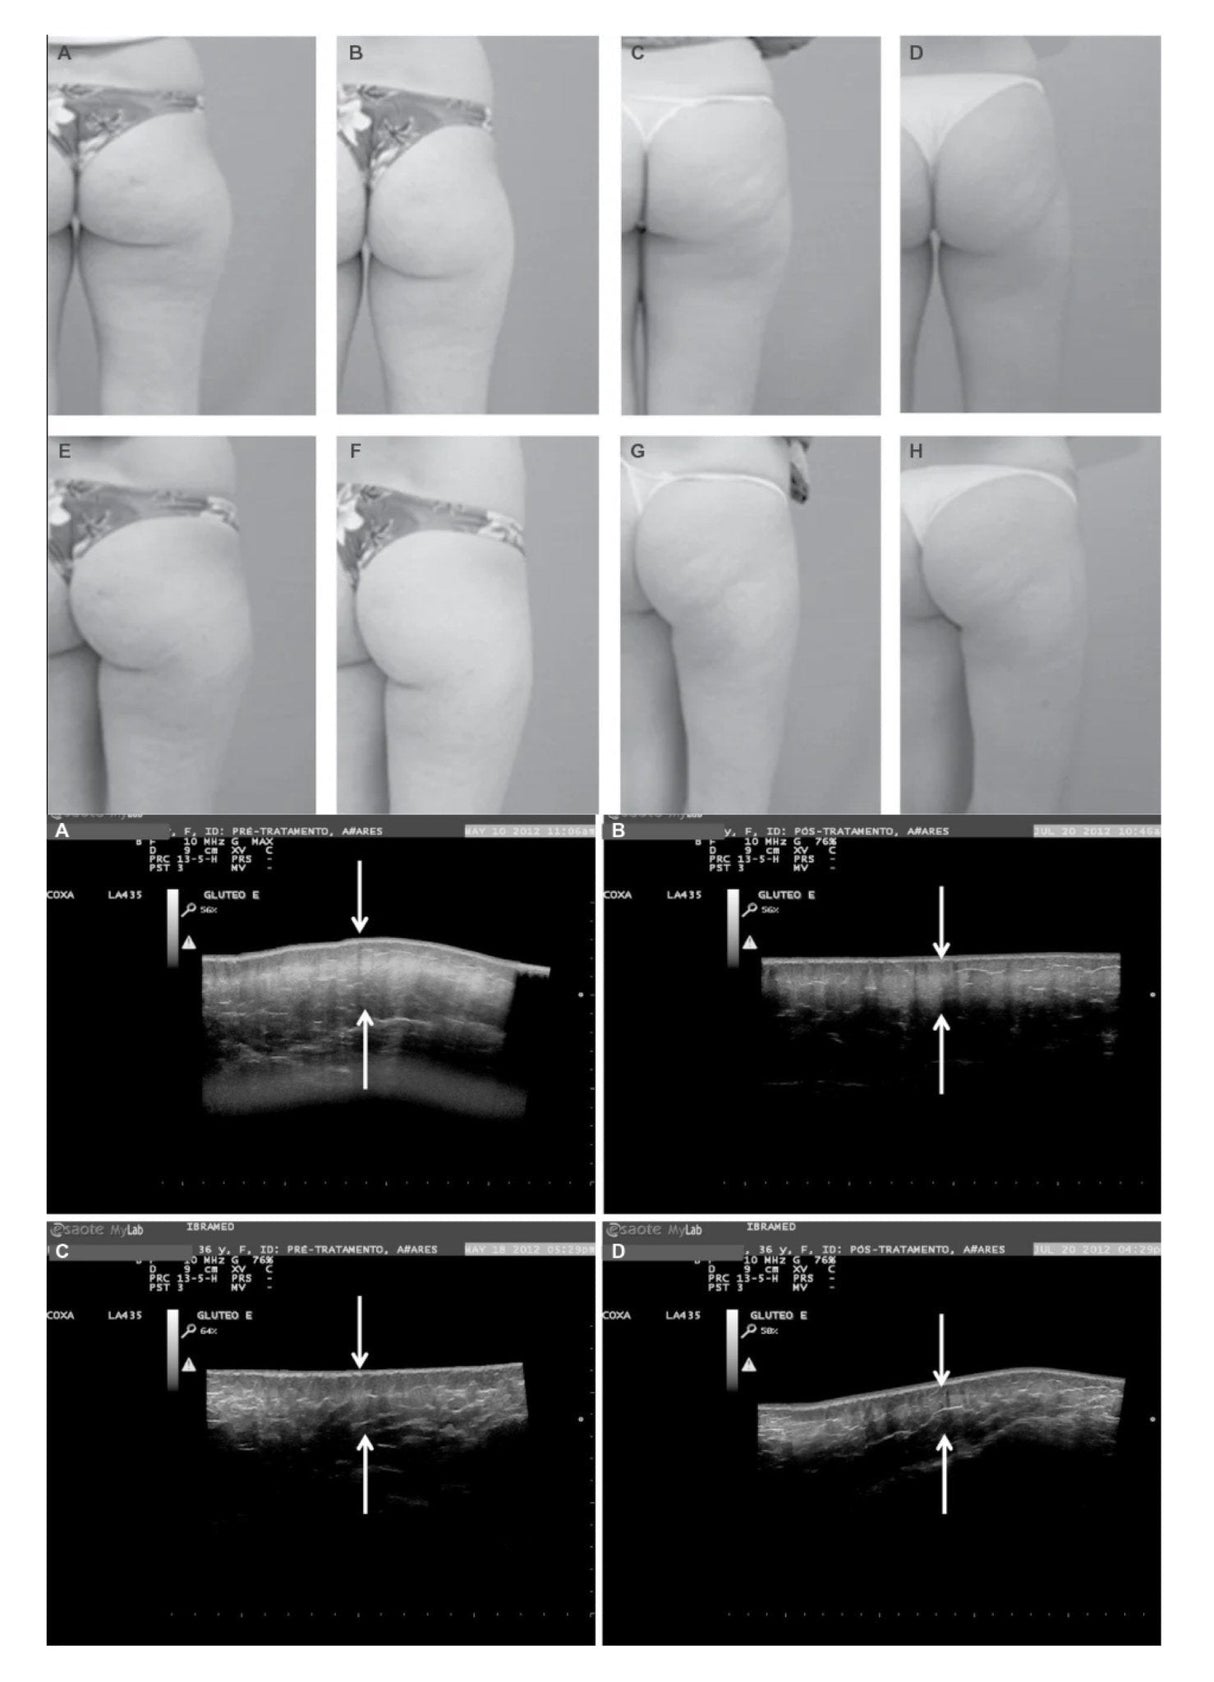

- Reducción de la celulitis y promoción de la elasticidad.

- Costa, A., et al. "Reducción de la celulitis mediante terapia con CO2". Revista de Medicina Estética.